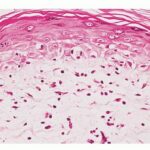

Large-plaque parapsoriasis and parapsoriasis variegata are best considered as early stages of cutaneous T-cell lymphoma/mycosis fungoides. The small-plaque parapsoriasis is also known as xanthoerythrodermia perstans of Crocker and as digitate dermatosis . Pink-to-yellow, slightly scaly, oval or elongated, often fingerprint-like patches 1 to 5 cm in diameter are symmetrically distributed over the trunk and the proximal portions of the extremities following the tension lines of the skin . The eruption is usually asymptomatic, has a chronic course, and tends to persist. In some instances, cases diagnosed originally as small-plaque type later showed reticulate pigmentation and atrophy and were reclassified as the large-plaque type . |